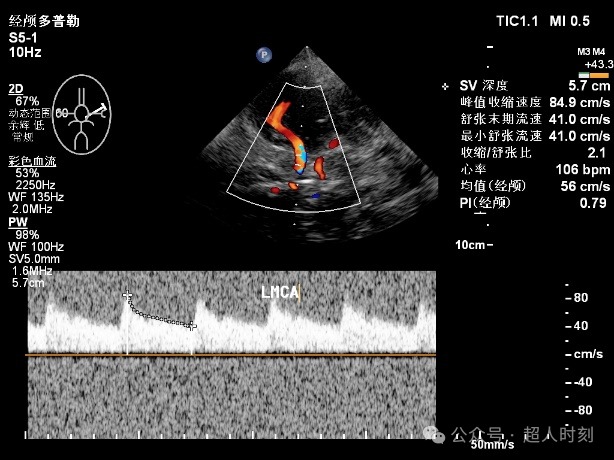

TCD只能提供简单的频谱图(如图2)

图2

TCCD(图3)不仅能够得到TCD那样的频谱图,还能直观看到血管的走行和血流的状态,是可视化医学的一个明显特征。